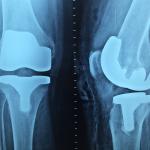

Loss of bone density can be a significant issue for adults later in life, especially for those with healthy lifestyles who are living longer than ever. So what's an essential way to build up strong bones while one can?